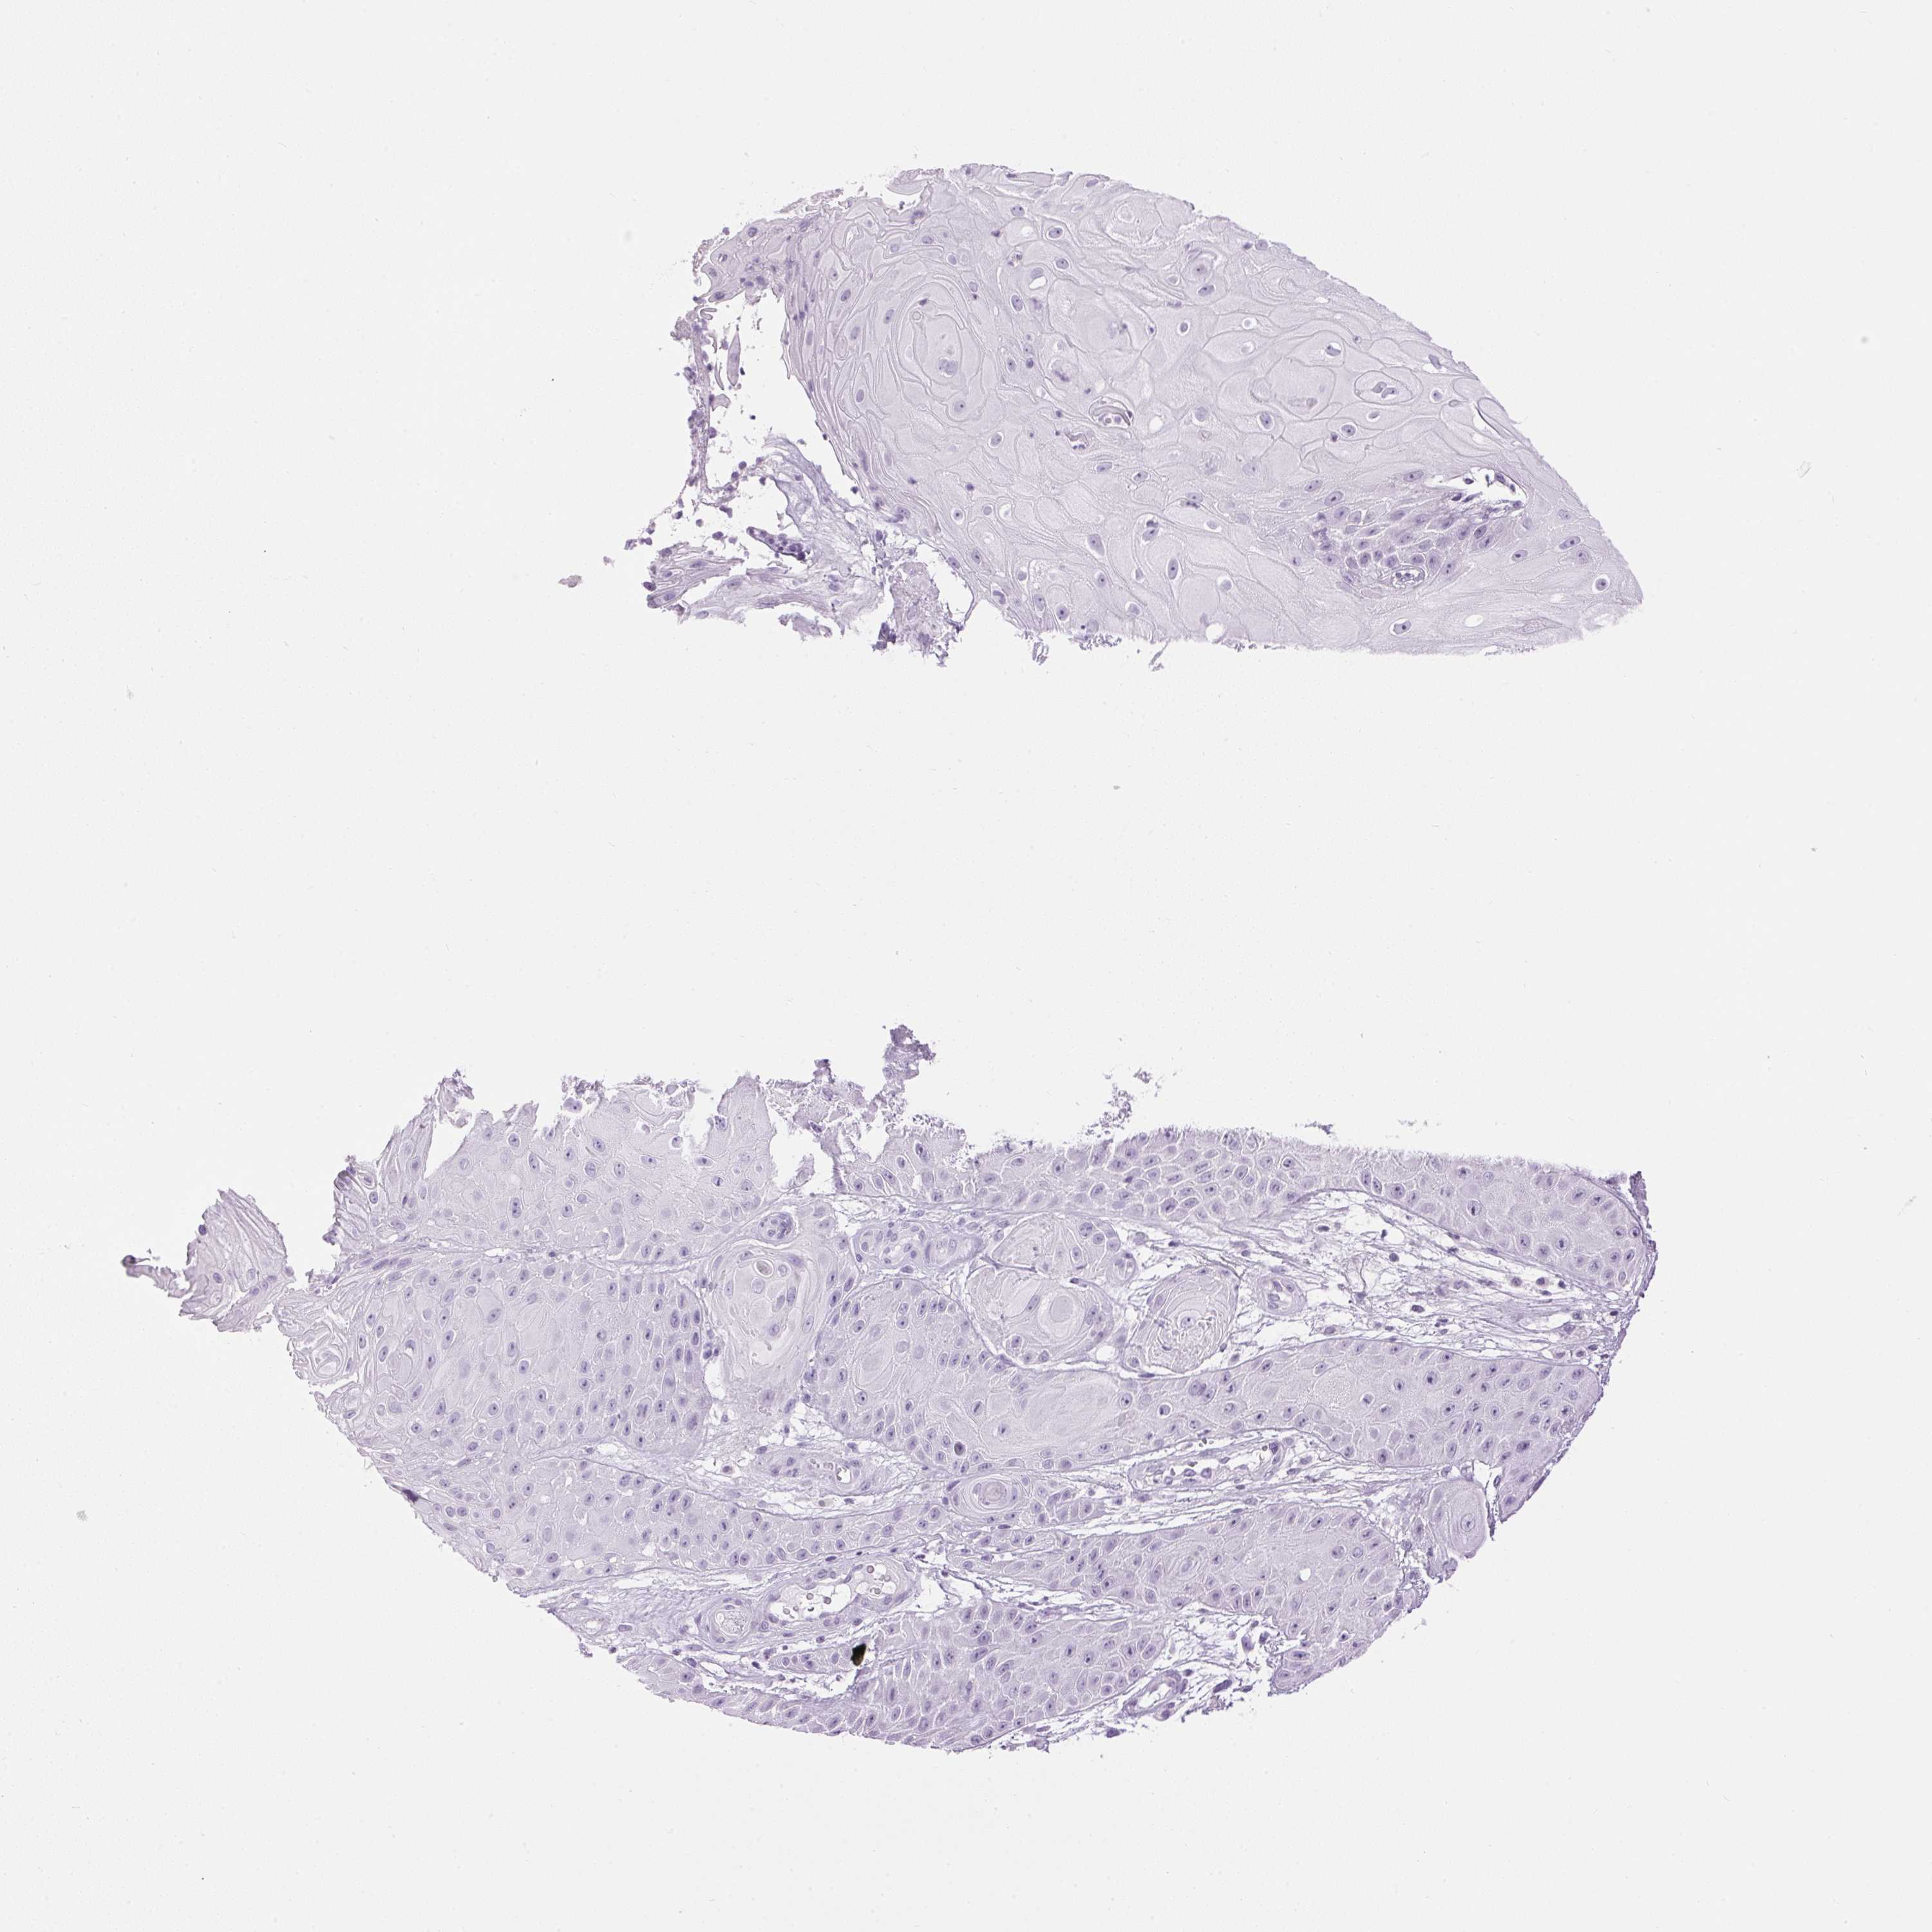

SKIN CANCER - Protein expressioni

A mouse-over function shows sample information and annotation data. Click on an image to view it in a full screen mode. Samples can be filtered based on level of antibody staining by selecting one or several of the following categories: high, medium, low and not detected. The assay and annotation is described here.

Antibody staining in the annotated cell types in the current human tissue is reported as not detected, low, medium, or high, based on conventional immunohistochemistry profiling in selected tissues. This score is based on the combination of the staining intensity and fraction of stained cells.

Each image is clickable and will lead to virtual microscopy that enables deeper exploration of all samples and also displays staining intensity scores, fraction scores and subcellular localization as well as patient and tissue information for each sample.

Antibody HPA063202

Staining

Medium

Moderate

>75%

Nuclear

Squamous cell carcinoma, NOS